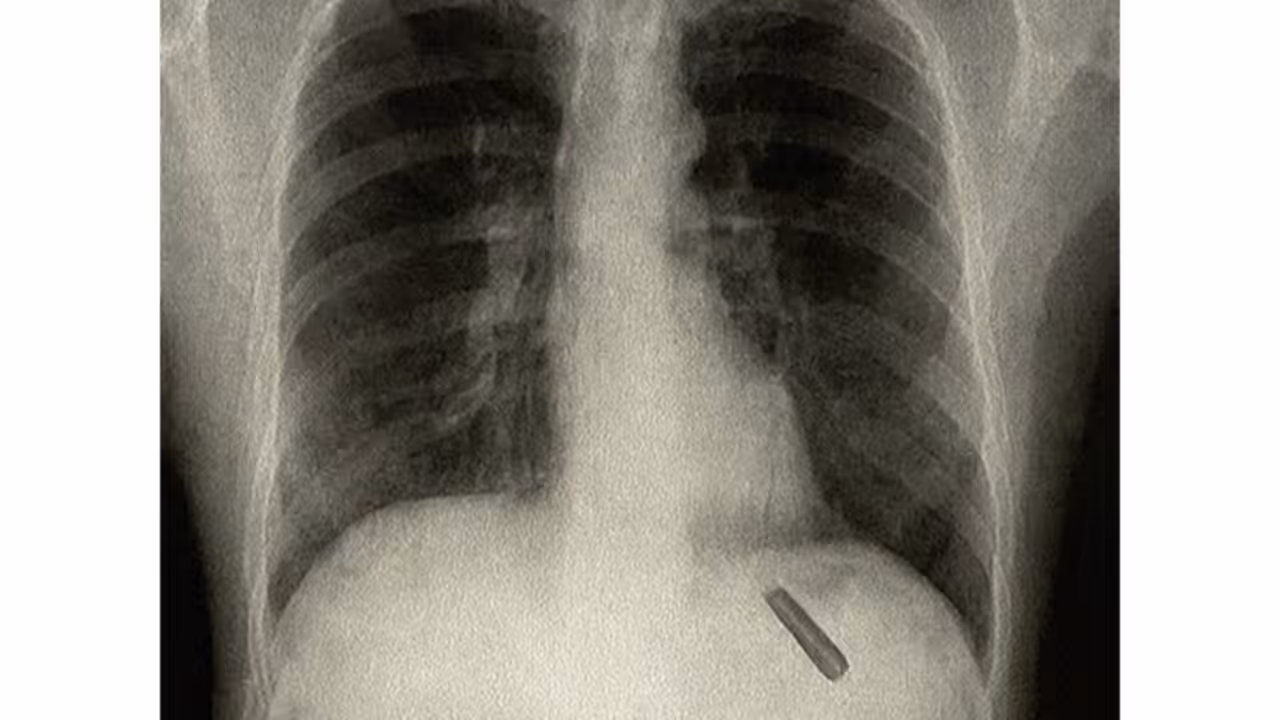

Doctors conducted detailed investigations, including an X-ray, which confirmed the presence of a foreign object inside his lung. Considering the risks, the thoracic surgery team led by Dr. Sabyasachi Bal, Chairperson of Thoracic Surgery at Sir Ganga Ram Hospital, decided to operate. During the surgery, doctors were astonished to find the pen cap intact and successfully removed it after 26 long years.